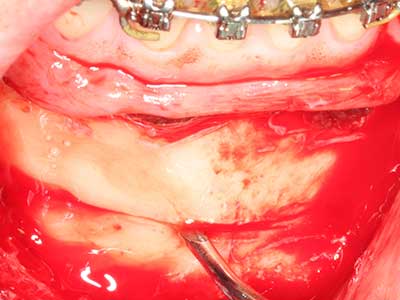

As shown in the past, basically any bone surgery procedure represents a possible indication for piezosurgery. Thus preparation of the mobile segment in distraction osteogenesis (Fig. 23-25) and sandwich osteotomy uses special attachments without endangering the blood supply to the crestal section, which is essential for the success of both techniques (Gonzalez-Garcia, Diniz-Freitas et al. 2008).

Purely orthodontic indications include orthognathic surgery, genioplasty (Fig. 27-30) and orbital decompression in patients with advanced endocrine orbitopathy as a result of Basedow’s disease (Ponto, Zwiener et al. 2014). Piezo devices are also used in maxillofacial surgery and to remove tumours at the base of the skull in various hospitals.